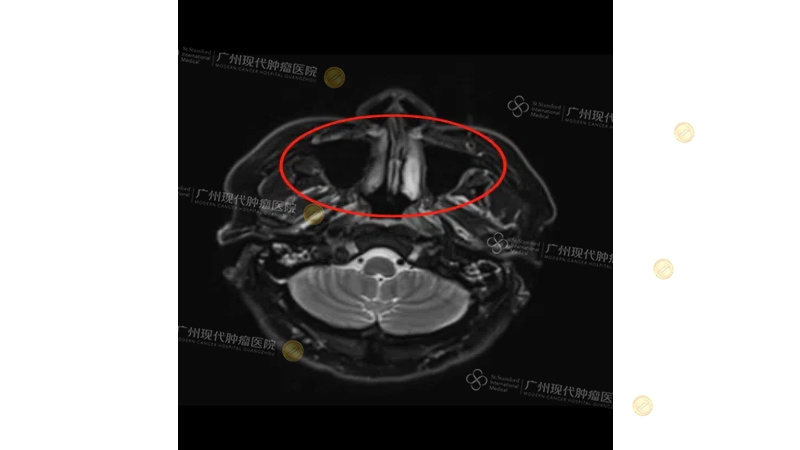

在实际案例中,向其德教授提到一位来自马来西亚的鼻咽癌患者——陈细睦:患者伴双侧颈部淋巴结转移,主肿瘤紧邻脑部,约3.8*2.7cm,局部治疗风险极高。向其德教授带领团队为其制定了以介入治疗为主的精准整合微创治疗方案。经4个月治疗后,CT检查结果显示鼻咽肿瘤活性消失,病灶基本清除,颈部淋巴转移灶也明显缩小。这一案例,充分体现了微创手段在解决复杂、难治病例中的独特价值。

(陈细睦治疗前CT)

(陈细睦治疗后CT)